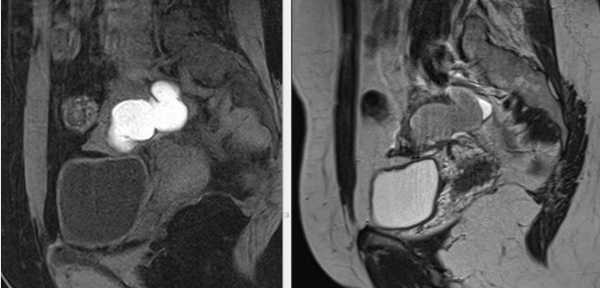

МРТ малого таза в сагиттальной плоскости. В структуре яичника отмечается неправильной формы эндометриоидная (“шоколадная”) киста, заполненная вязким геморрагическим содержимым.